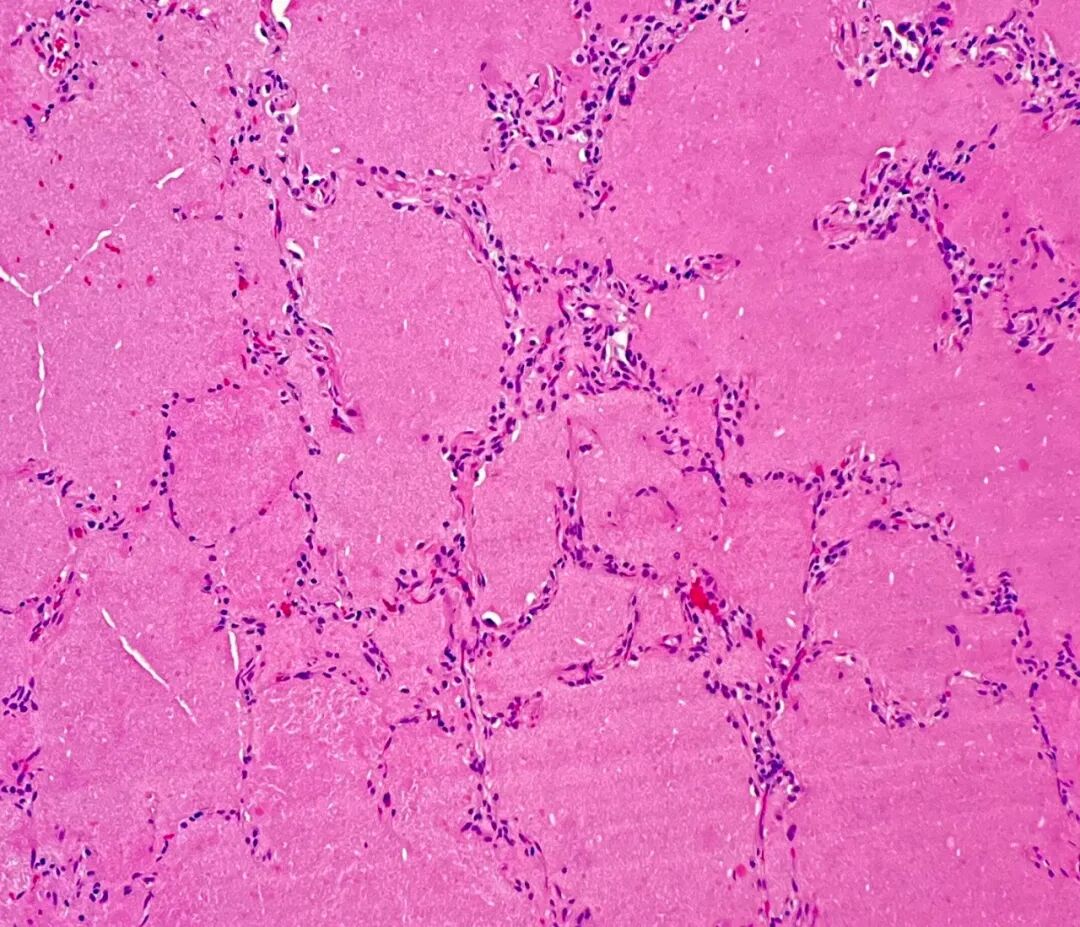

图4. 苏木精-伊红(H&E)染色显示,肺泡腔内充满弥漫性蛋白质样物质。

病理学检查对PAP的诊断具有高度敏感性和特异性。组织学上,可见小动脉和细支气管结构基本保留,炎症反应轻微或缺如,可因II型肺泡上皮细胞增生致部分间隔增厚。最具特征性的改变是,终末细支气管及肺泡腔内充满大量脂蛋白样物质,PAS染色呈强阳性,提示含有大量多糖及黏液物质。此发现符合表面活性物质代谢异常导致其积聚的病理生理过程。图4(H&E染色)显示肺泡腔内弥漫分布的蛋白质样物质。图5(PAS染色)则清晰显示了填充于终末支气管及肺泡腔内的PAS阳性物质,与相邻的正常肺组织形成鲜明对比,充分展现了PAP病例病理学检查的独特性和诊断价值。此外,Grocott-Gomori六胺银染色结果为阴性,排除了肺孢子菌感染(此为PAP的一个重要鉴别诊断)。与本病例的影像学表现不同,其病理学特征完全符合典型的PAP表现,从而确立了诊断。